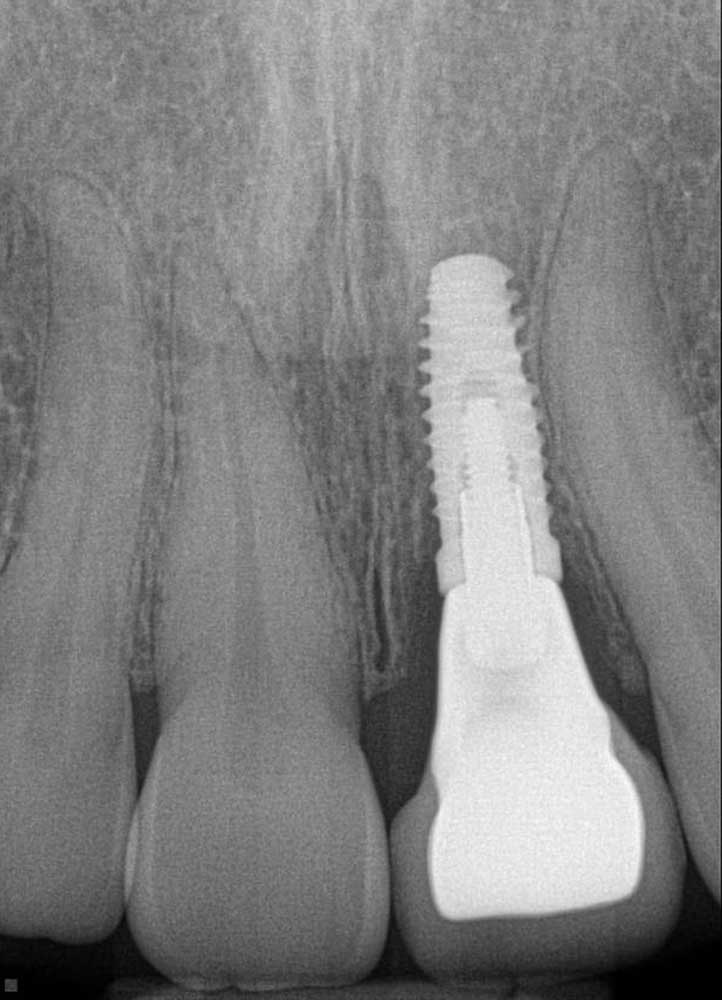

Gap restored with an implant

X-Ray showing gap restored with an implant